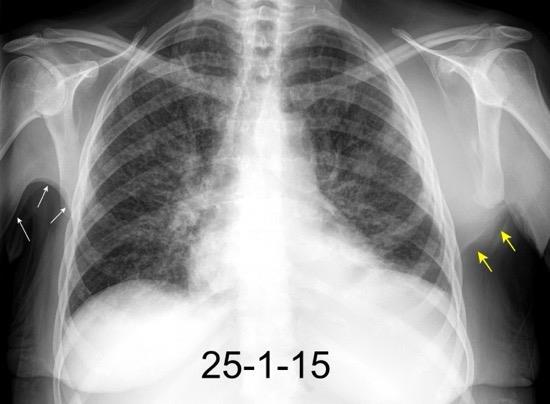

Masa axilar izquierda y derrame pleural derecho. Implantes pleurales, paraespinales . Ganglios en mamaria interna. Linfoma B difuso

Jaffe ES. Diagnosis and Classification of Lymphoma: Impact of Technical Advances.

2005. Masa pulmonar.

Nódulo en língula.

Cirugía de Ca .de mama hace 23 añosedema de brazo y ganglio en axila. ¡Metástasis!.